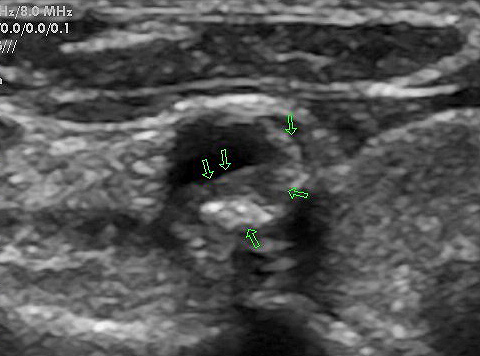

Auf den Bildern sehen Sie einerseits eine glatte Halsschlagader, die Sie schon als solche

erkennen können, weiter eine Halsschlagader mit beginnender Ablagerung (Plaques) und

eine Halsschlagader mit deutlichen Plaquebildungen bis insgesamt zu einer mindestens

70 %igen Verengung. Das erkennt man an dem schwarzen noch offenen Lumen.